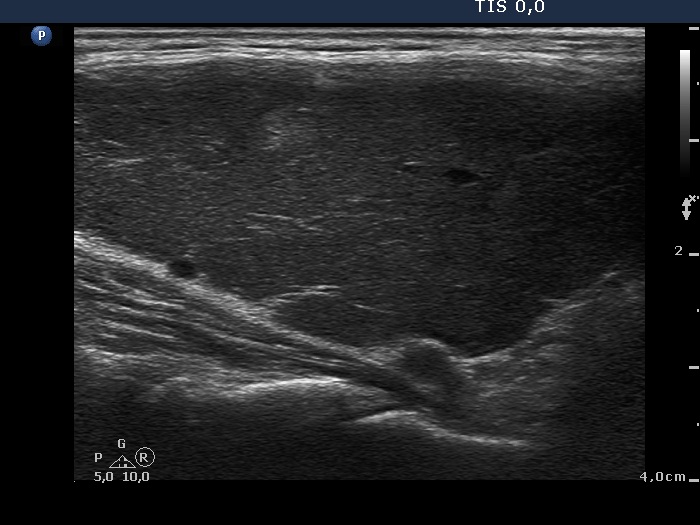

Consecutively operated patients with autoimmune thyroid disease - case 10 (1161)

Two months after the first examination (ultrasonographic picture 3)

Lower part of the right lobe, longitudinal scan. Note an echonormal islet.